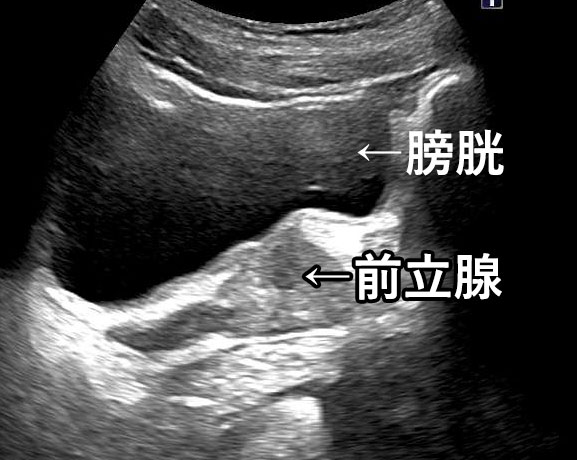

正常な前立腺のエコー画像

前⽴腺肥⼤症のエコー画像